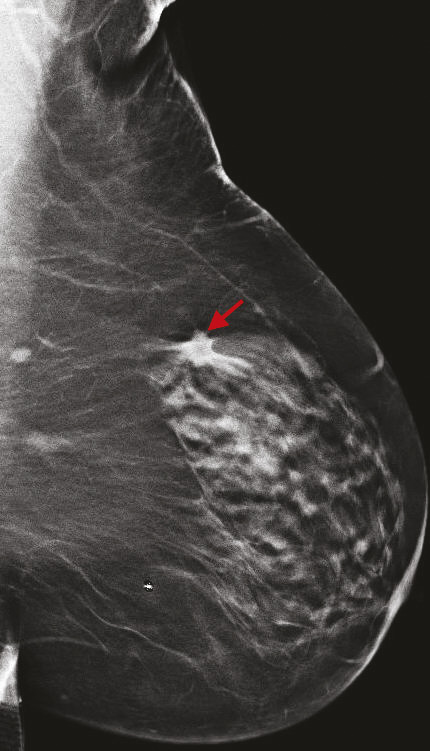

La tomosynthèse est une technique de mammographie développée depuis plus de 15 ans qui consiste non plus à acquérir deux images fixes du sein, mais un volume d’images, par un déplacement du tube de rayons X sur une angulation définie. Ainsi, le nombre d’images varie selon l’épaisseur du sein. L’avantage de cette technique est de s’affranchir d’une partie des effets masquants du tissu mammaire sur d’éventuelles lésions, et de mieux définir les contours des lésions bénignes et des cancers.

Cette technique permet d’augmenter le taux de détection des cancers, principalement invasifs, en particulier dans les seins denses de type C. Une récente étude prospective italienne a montré que la tomosynthèse mammaire deux incidences (face, oblique), associée à la vue synthétique (image 2D reconstruite à partir du volume 3D), permettait d’augmenter significativement le taux de cancers.8 Dans cette étude, 16 666 femmes asymptomatiques âgées de 50 à 69 ans ont été dépistées dans le programme de dépistage de Vérone avec une tomosynthèse deux incidences, comportant une analyse complémentaire de la vue synthétique. Les résultats ont été comparés à ceux de la précédente cohorte de dépistage de 2014, où les mammographies avaient été acquises uniquement en 2D (14 443 femmes).9 Le programme avec tomosynthèse et vue synthétique a permis une augmentation de détection de cancers invasifs significatifs par rapport au programme de dépistage 2D, avec un taux de détection de 9,30 versus 5,41 cancers pour 1 000 femmes. Ce qui est intéressant est que les cancers dépistés étaient plus souvent des cancers invasifs de stade 1 (72,3 % avec la tomosynthèse vs 50 % avec la mammographie 2D), avec moins de cancers in situ (9 % avec la tomosynthèse vs 26,9 % avec la mammographie 2D). Le taux de rappel était similaire entre les deux techniques (4 % pour la tomosynthèse vs 4,2 % pour la mammographie 2D). Ces résultats sont en accord avec les principales études prospectives et rétrospectives comparant l’apport de la tomosynthèse par rapport à la mammographie 2D.10 11